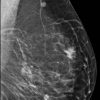

Ung thư vú

» Thông tin: Nữ giới – 56 tuổi.

» Lâm sàng: Khối tuyến vú.